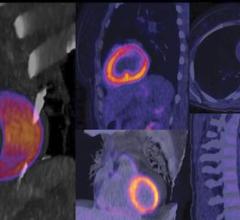

April 21, 2021 — Meeting the growing cardiovascular needs of healthcare providers today, Canon Medical Systems USA, Inc ...

April 6, 2021 — In 2020, the International Agency for Research on Cancer of the World Health Organization stated that ...

March 24, 2021 — RSIP Vision, a leading innovator in medical imaging through advanced artificial intelligence (AI) and ...